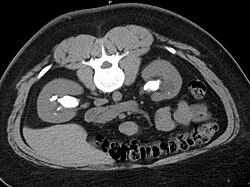

Bilateral staghorn calculi as seen on CT

Otherwise a noncontrast helical CT scan with 5 millimeters (0.2 in) sections is the diagnostic method to use to detect kidney stones and confirm the diagnosis of kidney stone disease.[13][47][51][52][7] Near all stones are detectable on CT scans with the exception of those composed of certain drug residues in the urine,[53] such as from indinavir. Calcium-containing stones are relatively radiodense, and they can often be detected by a traditional radiograph of the abdomen that includes the kidneys, ureters, and bladder (KUB film).[53] Some 60% of all renal stones are radiopaque.[51][54] In general, calcium phosphate stones have the greatest density, followed by calcium oxalate and magnesium ammonium phosphate stones. Cystine calculi are only faintly radiodense, while uric acid stones are usually entirely radiolucent.[55]

About 10–15% of urinary calculi are composed of struvite (ammonium magnesium phosphate, NH4MgPO4·6H2O).[64] Struvite stones (also known as "infection stones," urease, or triple-phosphate stones) form most often in the presence of infection by urea-splitting bacteria. Using the enzyme urease, these organisms metabolize urea into ammonia and carbon dioxide. This alkalinizes the urine, resulting in favorable conditions for the formation of struvite stones. Proteus mirabilis, Proteus vulgaris, and Morganella morganii are the most common organisms isolated; less common organisms include Ureaplasma urealyticum and some species of Providencia, Klebsiella, Serratia, and Enterobacter. These infection stones are commonly observed in people who have factors that predispose them to urinary tract infections, such as those with spinal cord injury and other forms of neurogenic bladder, ileal conduit urinary diversion, vesicoureteral reflux, and obstructive uropathies. They are also commonly seen in people with underlying metabolic disorders, such as idiopathic hypercalciuria, hyperparathyroidism, and gout. Infection stones can grow rapidly, forming large calyceal staghorn (antler-shaped) calculi requiring invasive surgery such as percutaneous nephrolithotomy for definitive treatment.[64]

Stones that are large enough to fill out the renal calyces are called staghorn stones, and are composed of struvite in a vast majority of cases, which forms only in the presence of urease-forming bacteria. Other forms that can possibly grow to become staghorn stones are those composed of cystine, calcium oxalate monohydrate, and uric acid.[74]